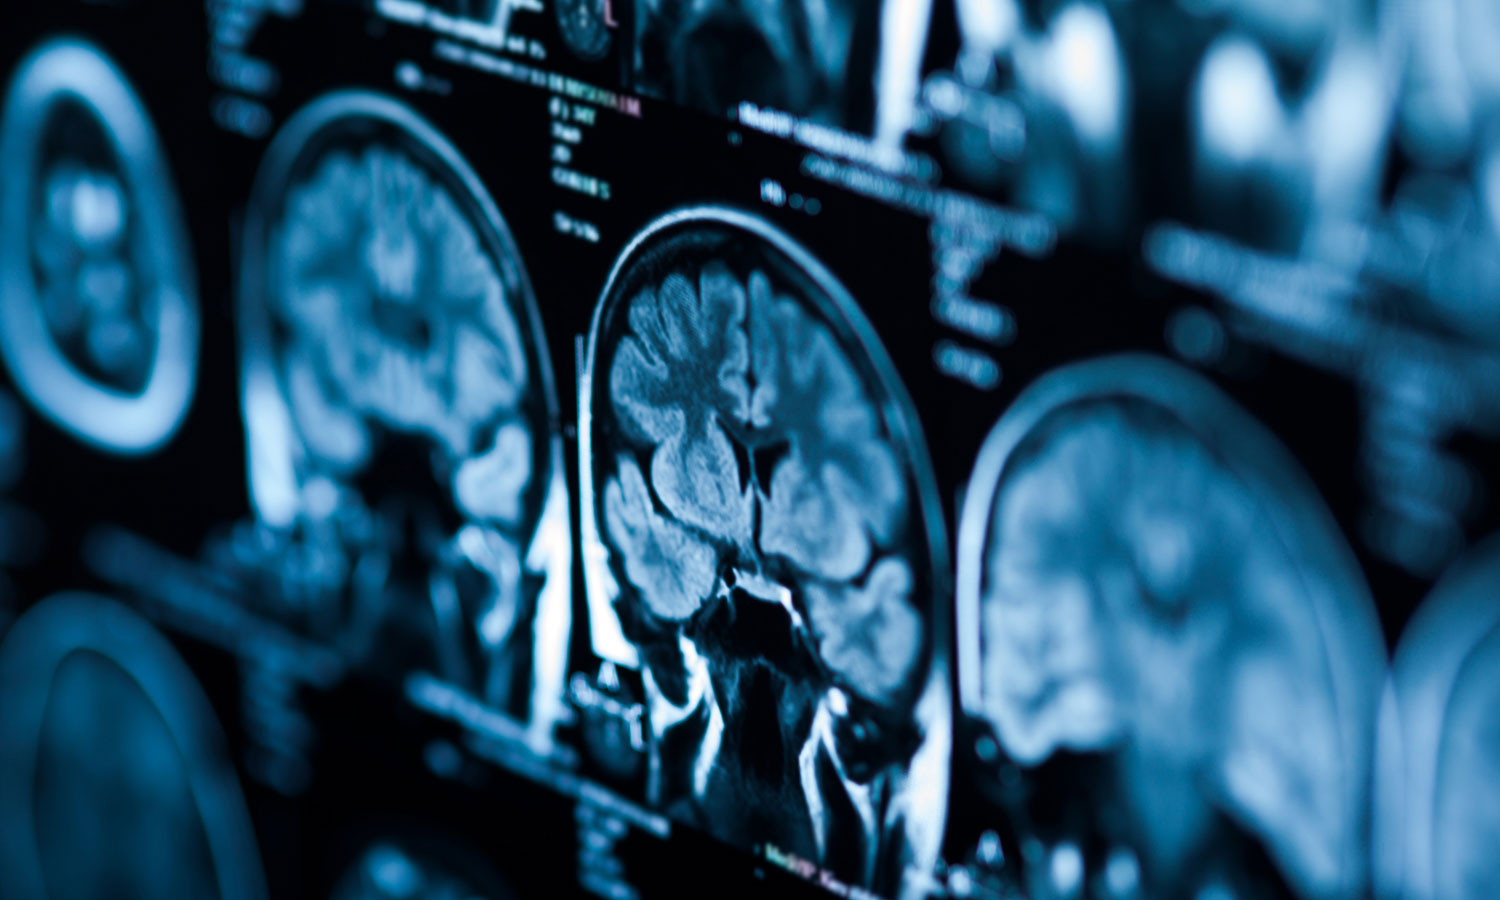

Advanced imaging

Our physicians use the latest technology in advanced imaging, including computed tomography (CT), advanced magnetic resonance imaging (MRI), functional MRI and magnetic resonance spectroscopy (MRS), and positron emission tomography (PET) as initial diagnostic modalities.